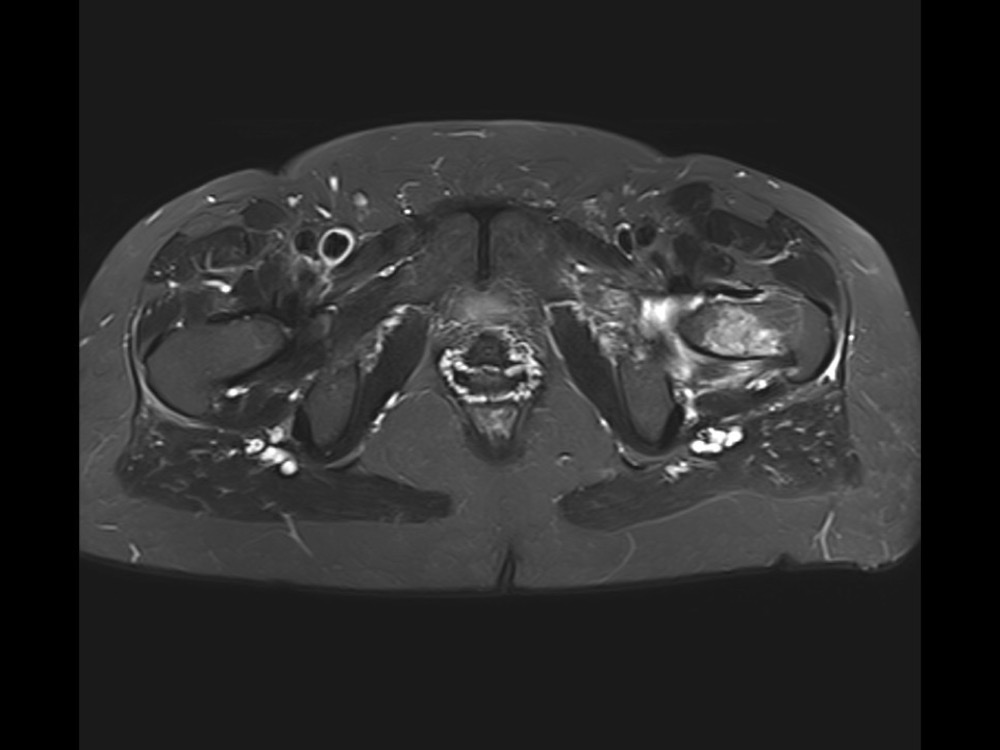

Douleurs de hanche

Linda Ouerd 06/11/2019